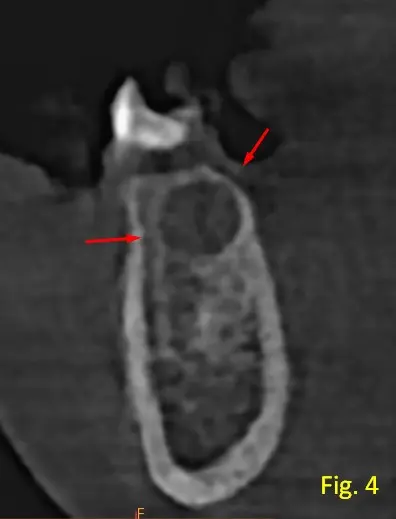

Adempas se visualiza lesión más pequeña, entre pieza dentaria 44-43 (ver figura 4), que no es compatible a espacios medulares del apciente, debido a su tamaño.